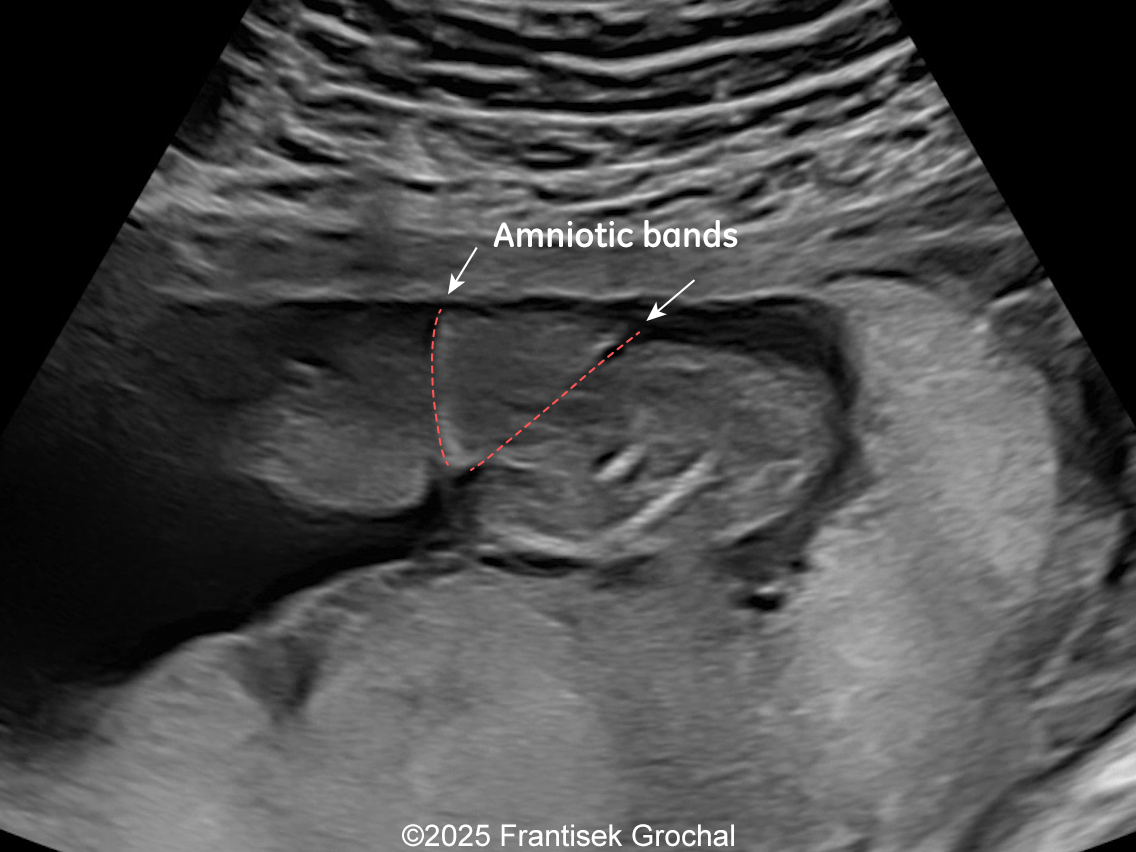

Constriction of fetal torso by two stripes of the amniotic bands

Image 1 Constriction of fetal torso by two stripes of the amniotic bands

Image 3 Constriction of fetal torso by two stripes of the amniotic bands

• Constriction of fetal torso by two strips of amniotic band